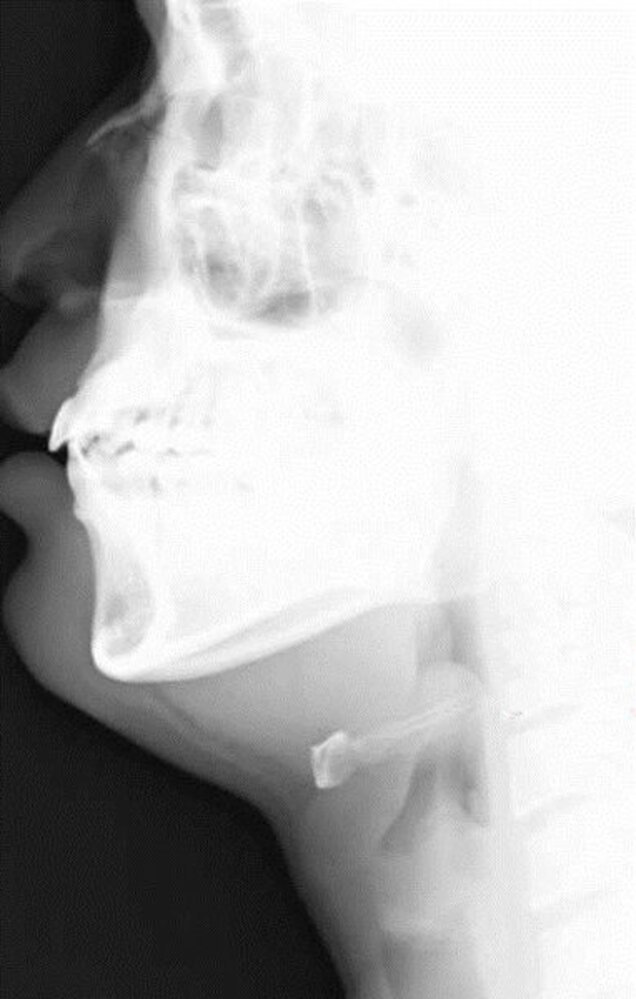

X-ray neck (portable; lateral view)